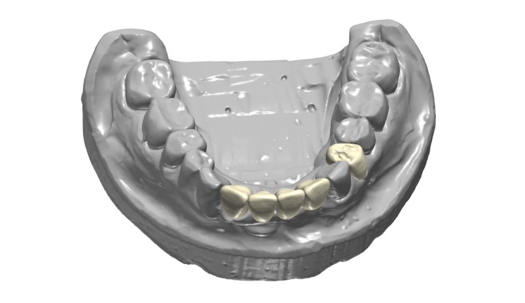

After completing an initial diagnostic appointment, a patient accepted three single-unit full-contour zirconia crowns that were milled from the digital impression and cut back for porcelain application. The application by a technician is analog dentistry. The ability of a dental laboratory to scan an analog crown-and-bridge impression is called converting an analog impression to a digital impression. The workflow after the conversion has become digitized. A dental model is virtually created with computer software, and a full crown proposal is fabricated for inspection virtually before the crown is milled (Figure 2). Due to the color of the digitized impression, the margins of the crown preparations are more easily and rapidly identified. The laboratory will also 3D print a working model, which will be used to develop the morphology of the final restoration by hand placement of porcelain (Figure 3). The decision to prescribe a full contour zirconia crown with cutback for porcelain application or complete full contour zirconia crowns lies solely on the attending dentist.9 A discussion with the patient before preparation of the teeth is imperative. After the discussion, the patient requested the zirconia copings with cutback and porcelain application for the posterior crowns (Figure 4 and Figure 5).

Fig 2. Digital impression and proposal of zirconia cutback before porcelain application.

Figure 2

Fig 3. 3D-printed model.

Figure 3

Fig 4. Zirconia with cutback for porcelain application.

Figure 4

Fig 5. Occlusal view of completed zirconia with porcelain application on teeth Nos. 29, 30, and 31.

Figure 5